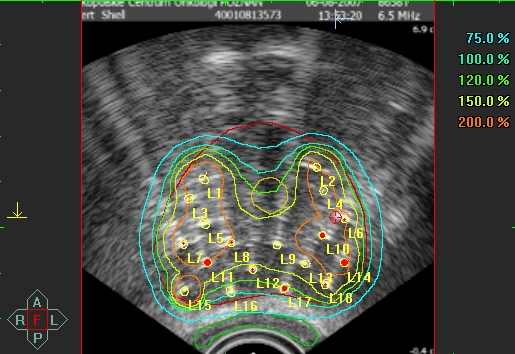

Rozkład dawki na tle zarysu USG gruczołu krokowego, widoczne izodozy, lokalizacja igieł